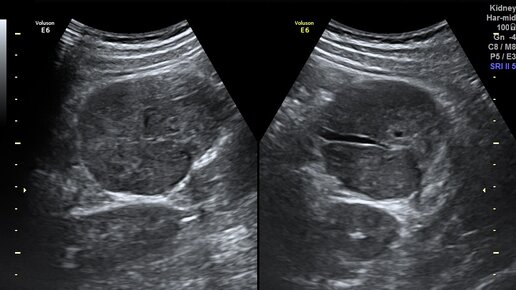

😷- Что то беспокоит? 😢- Доктор, у меня хронический пиелонефрит, видимо обострение. 👓Ок, будем посмотреть. Левая почка без особенностей, расположена внизу экрана. Селезёнка не изменена. 🌑А вот в верхней части видно образование округлой формы, сосудами по центру и воротами. При надавливании датчиком болезненно. Размером чуть больше 6см в диаметре...